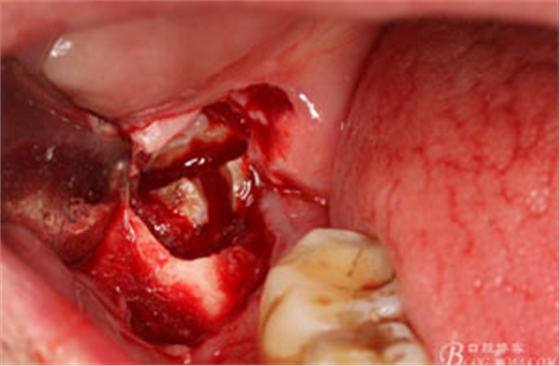

圖6.行角形瓣切開、翻瓣、暴露骨面,可見48牙冠表面有炎性肉芽組織

圖7.高速牙鉆去骨。逐漸可見48的牙冠

圖8.刮除牙冠表面的肉芽組織后,可見48 的牙冠